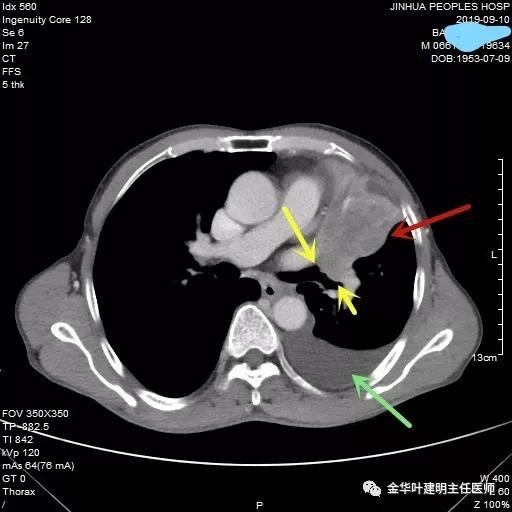

黄色箭头示肿瘤阻塞左上叶开口

黄色箭头示左肺下叶支气管外壁受累,没有间隙